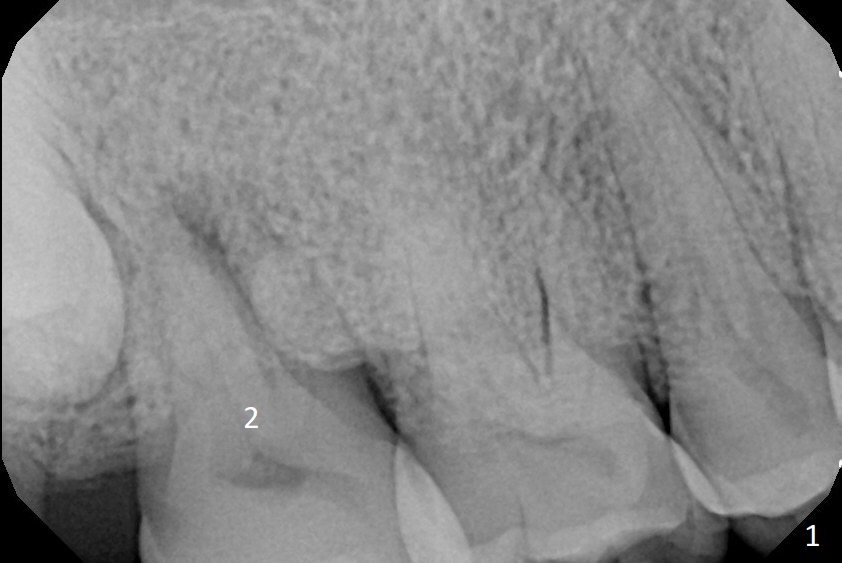

A 67-year-old man has pain associated with the tooth #2 with distal deep pockets (Fig.1), consistent with root fracture. The abnormal force may arise from the mesioangular lower 3rd molar (Fig.2 arrow). To avoid damage to the upper 3rd molar, osteotomy will be initiated obliquely with starter drill in the mesial slope of the socket (Fig.3 red). Once the starter drill makes a short entry, use 2 mm drill to change trajectory (Fig.4). Due to the uneven wall, an implant is expected to be placed distally by itself (Fig.5). The bone height is ~18 mm. If the patient agrees, remove the lower 3rd molar (Fig.5 black area).